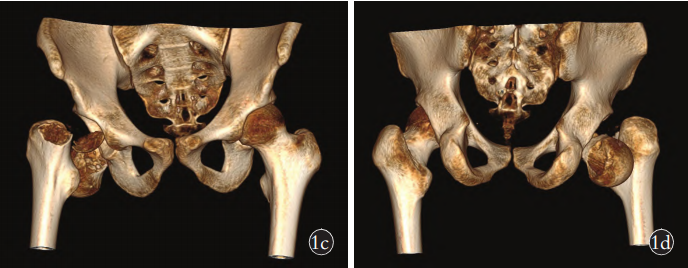

搞定双侧大面积股骨头坏死,原来这么简单!